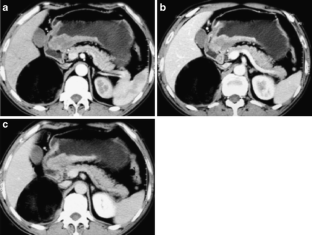

Fig. 2